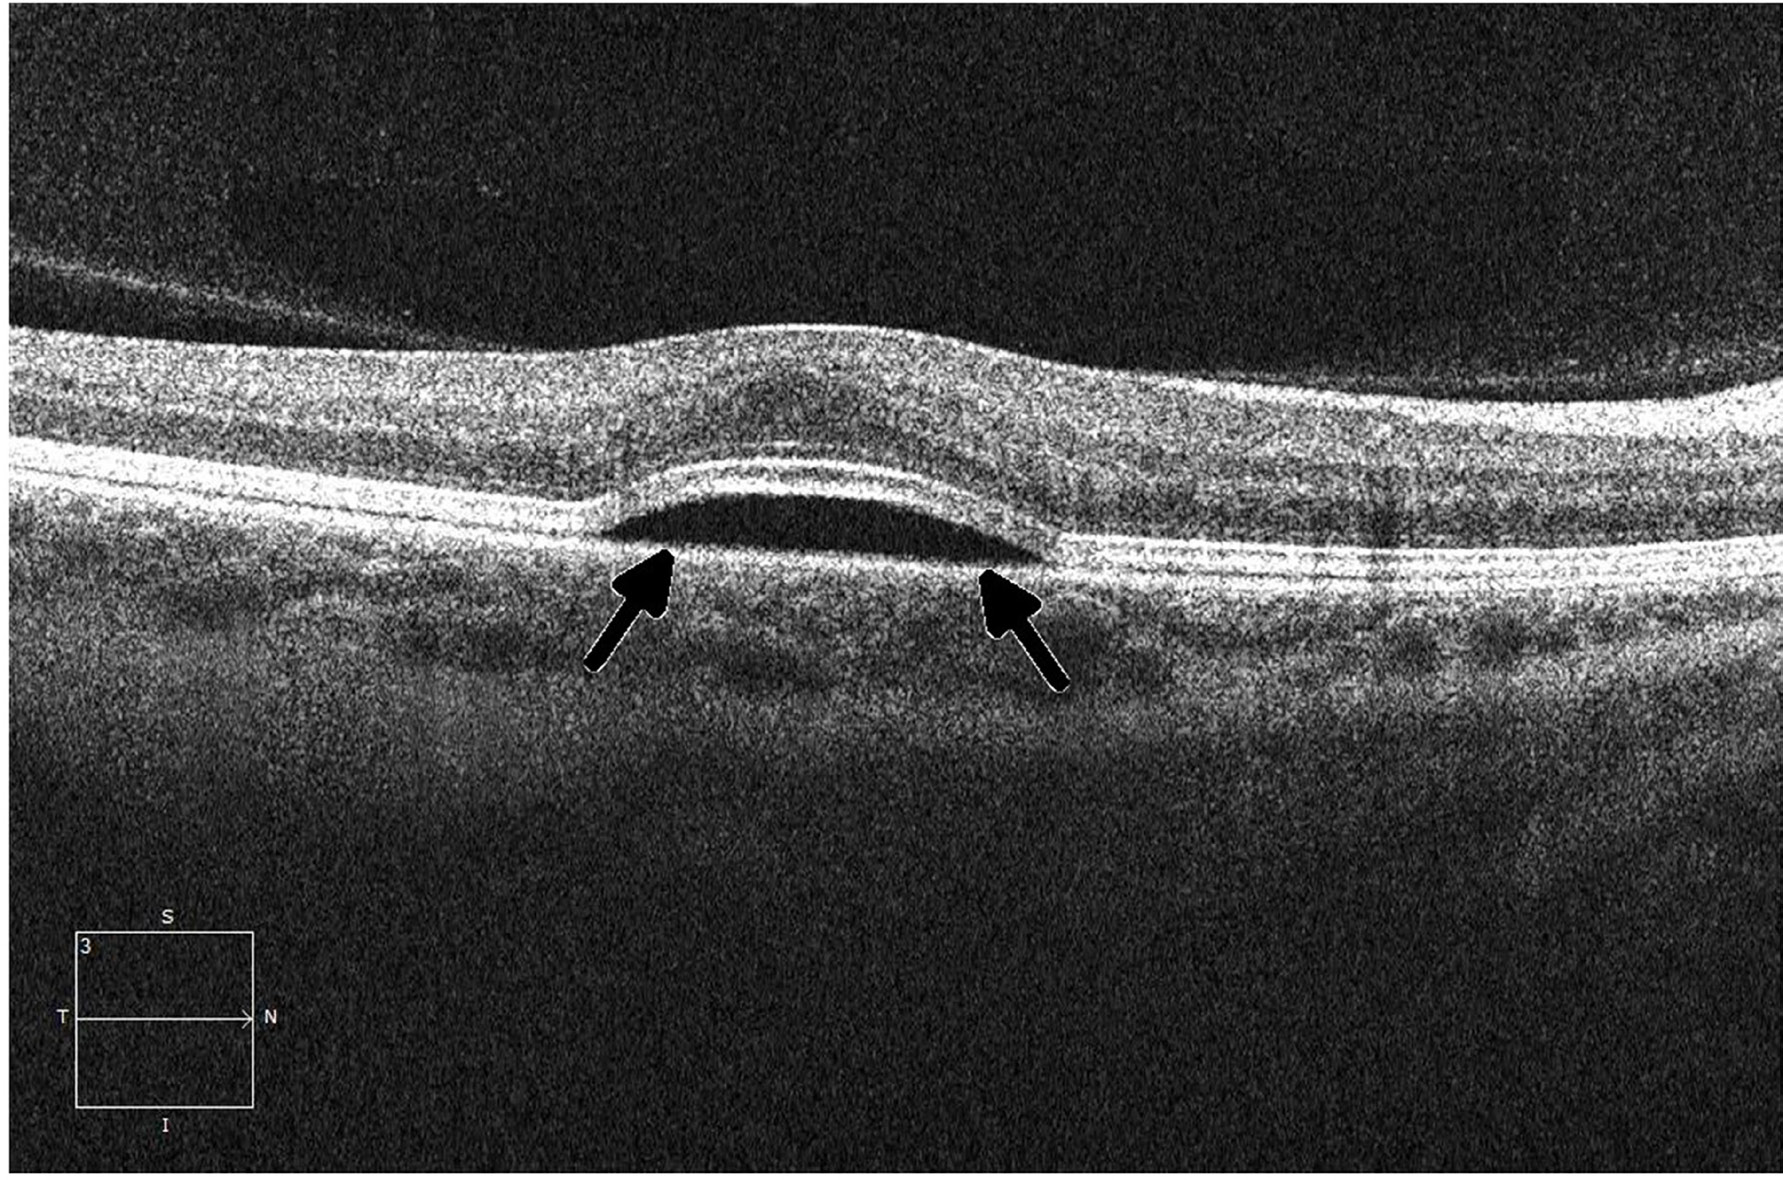

Figure 5: Ocular coherence tomography (OCT) displays a perpendicular cut through the retina in a patient with metastatic melanoma undergoing therapy with a small-molecule ERK inhibitor, demonstrating central serous retinopathy with subretinal fluid buildup (arrows).